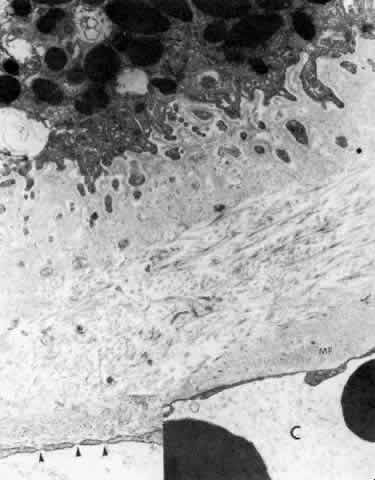

Fig. 27. Ciliary body stroma under the processes, anterior pars plicata. Even at age 19, the basement membrane is thick. Collagen and other fine filaments fill the narrow space between epithelium and fenestrated capillary wall (C). Inset. Arrowheads indicate fenestrae in wall. Clumps of tubular microfibrils (MF) of the elastic system are closely associated with the capillary wall. (X 17,300; inset, X 43,000)

THE ANTERIOR CILIARY BODY